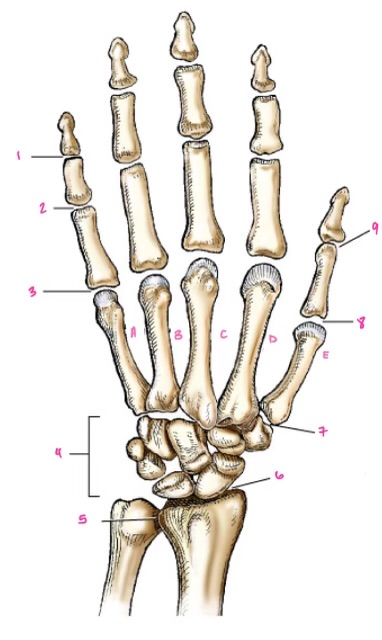

1

1

Hamate

2

2

Capitate

3

3

pisiform

4

9

Trapezoid

5

10

Trapezium

6

11

Scaphoid

7

14

Lunate

8

15

Triquetrum

9

16

Pisiform

10

17

Capitate

11

18

Hamate

1

Distal interphalangeal

13

2

Proximal Interphalangeal

14

3

Metacarpophalangeal

15

4

Intercapals

16

5

Distal radioulnar

17

6

Radiocarpal

18

7

Carpometacarpals

19

8

Metacarpophalangeal

20

9

Interphalangeal

7

Trapezoid

22

8

Trapzium

23

9

Capitate

24

10

Scaphoid

25

11

Lunate

26

13

Carpus

27

14

Triquetrul

28

15

Hamate

29

16

Metacarpus

30

17

Phalanxes